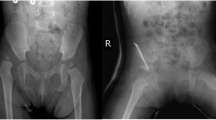

The study involved a cohort of 25 Tibetan pediatric patients diagnosed with DDH at the People’s Hospital of Tibet between January 2021 and March 2022. Inclusion in the study required a confirmed diagnosis of one of the following: (1) a complete hip joint dislocation, with no contact between the original articulating surfaces; (2) a hip joint subluxation, with partial contact maintained between the articulating surfaces; or (3) acetabular dysplasia, characterized by insufficient development of the acetabulum. The diagnosis was rendered by seasoned pediatric orthopedic specialists based on comprehensive medical evaluations, which included assessments of abnormal gait patterns such as limping or Trendelenburg gait. Physical examinations for asymmetrical gluteal folds or thigh skin creases were also conducted. Additional clinical signs considered were the pronounced elevation and lateral displacement of the greater trochanters, restricted abduction of the hip joint, and positive Ortolani, Barlow, Allis, or Galeazzi signs. Diagnostic confirmation was achieved through X-ray imaging. Cases with concurrent chronic diseases or other musculoskeletal disorders were meticulously excluded to maintain the study’s focus on isolated DDH. The control group comprised healthy Tibetan children who underwent routine health screenings at the People’s Hospital of Tibet concurrently with the study period and exhibited no abnormalities. The selection of control subjects was age and gender-matched to the case group to ensure comparability.

The average age of the children enrolled was 19.9 ± 9.1 months. The altitude of residence was 4101.9 ± 344.7 m. None had a family history of DDH. The ratio of girls to boys was 18:7. There were 2 cases (8%) of oligohydramnios during the fetal period, 1 case (4%) of post-term birth, and 23 cases (92%) were vaginal deliveries, all of which were cephalic presentations. Four (16%) were the first birth of the mother. The average birth weight was 3.5 ± 0.5 kg, with 9 (36%) weighing more than 4 kg at birth. Eleven (44%) were swaddled with tight wrappings, such as candle wraps during infancy. Among the 25 children, the number of cases with affected left hip, right hip, or both hips were 7, 8, and 11, respectively. Twenty-two (88%) underwent open surgical treatment after diagnosis. (Table 1).